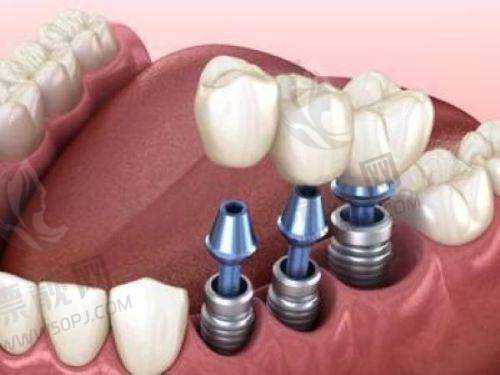

十、罗强口腔连锁种植院:懂你牙齿的城市种牙团队

这家口腔连锁在杭州多个区域设有分院,院长田宗从业十多年,曾进修于上海九院。机构主打精良数字导板进行种植诊断预判,尤其针对多年缺牙及顾虑术后调适的中年层客户建立专属治疗计划。 特色:术前数字模拟种植,全流程可视+追踪。 适合人群:错过黄金修复期、需高质量长期方案者。